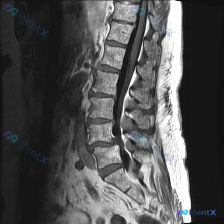

整理了一份影像分析的资料,有点意思,抛出来大家讨论下: - 影像序列是腰椎MRI T2加权矢状位 - 明确的阳性发现:L4/L5、L5/S1椎间盘明显脱水退变(黑盘征),均有后缘突出,硬膜囊受压;部分终板有退变性信号改变,脊髓圆锥位置正常,椎旁未见明显肿块/脓肿 - 但有个关键的「矛盾」或者说「局限...